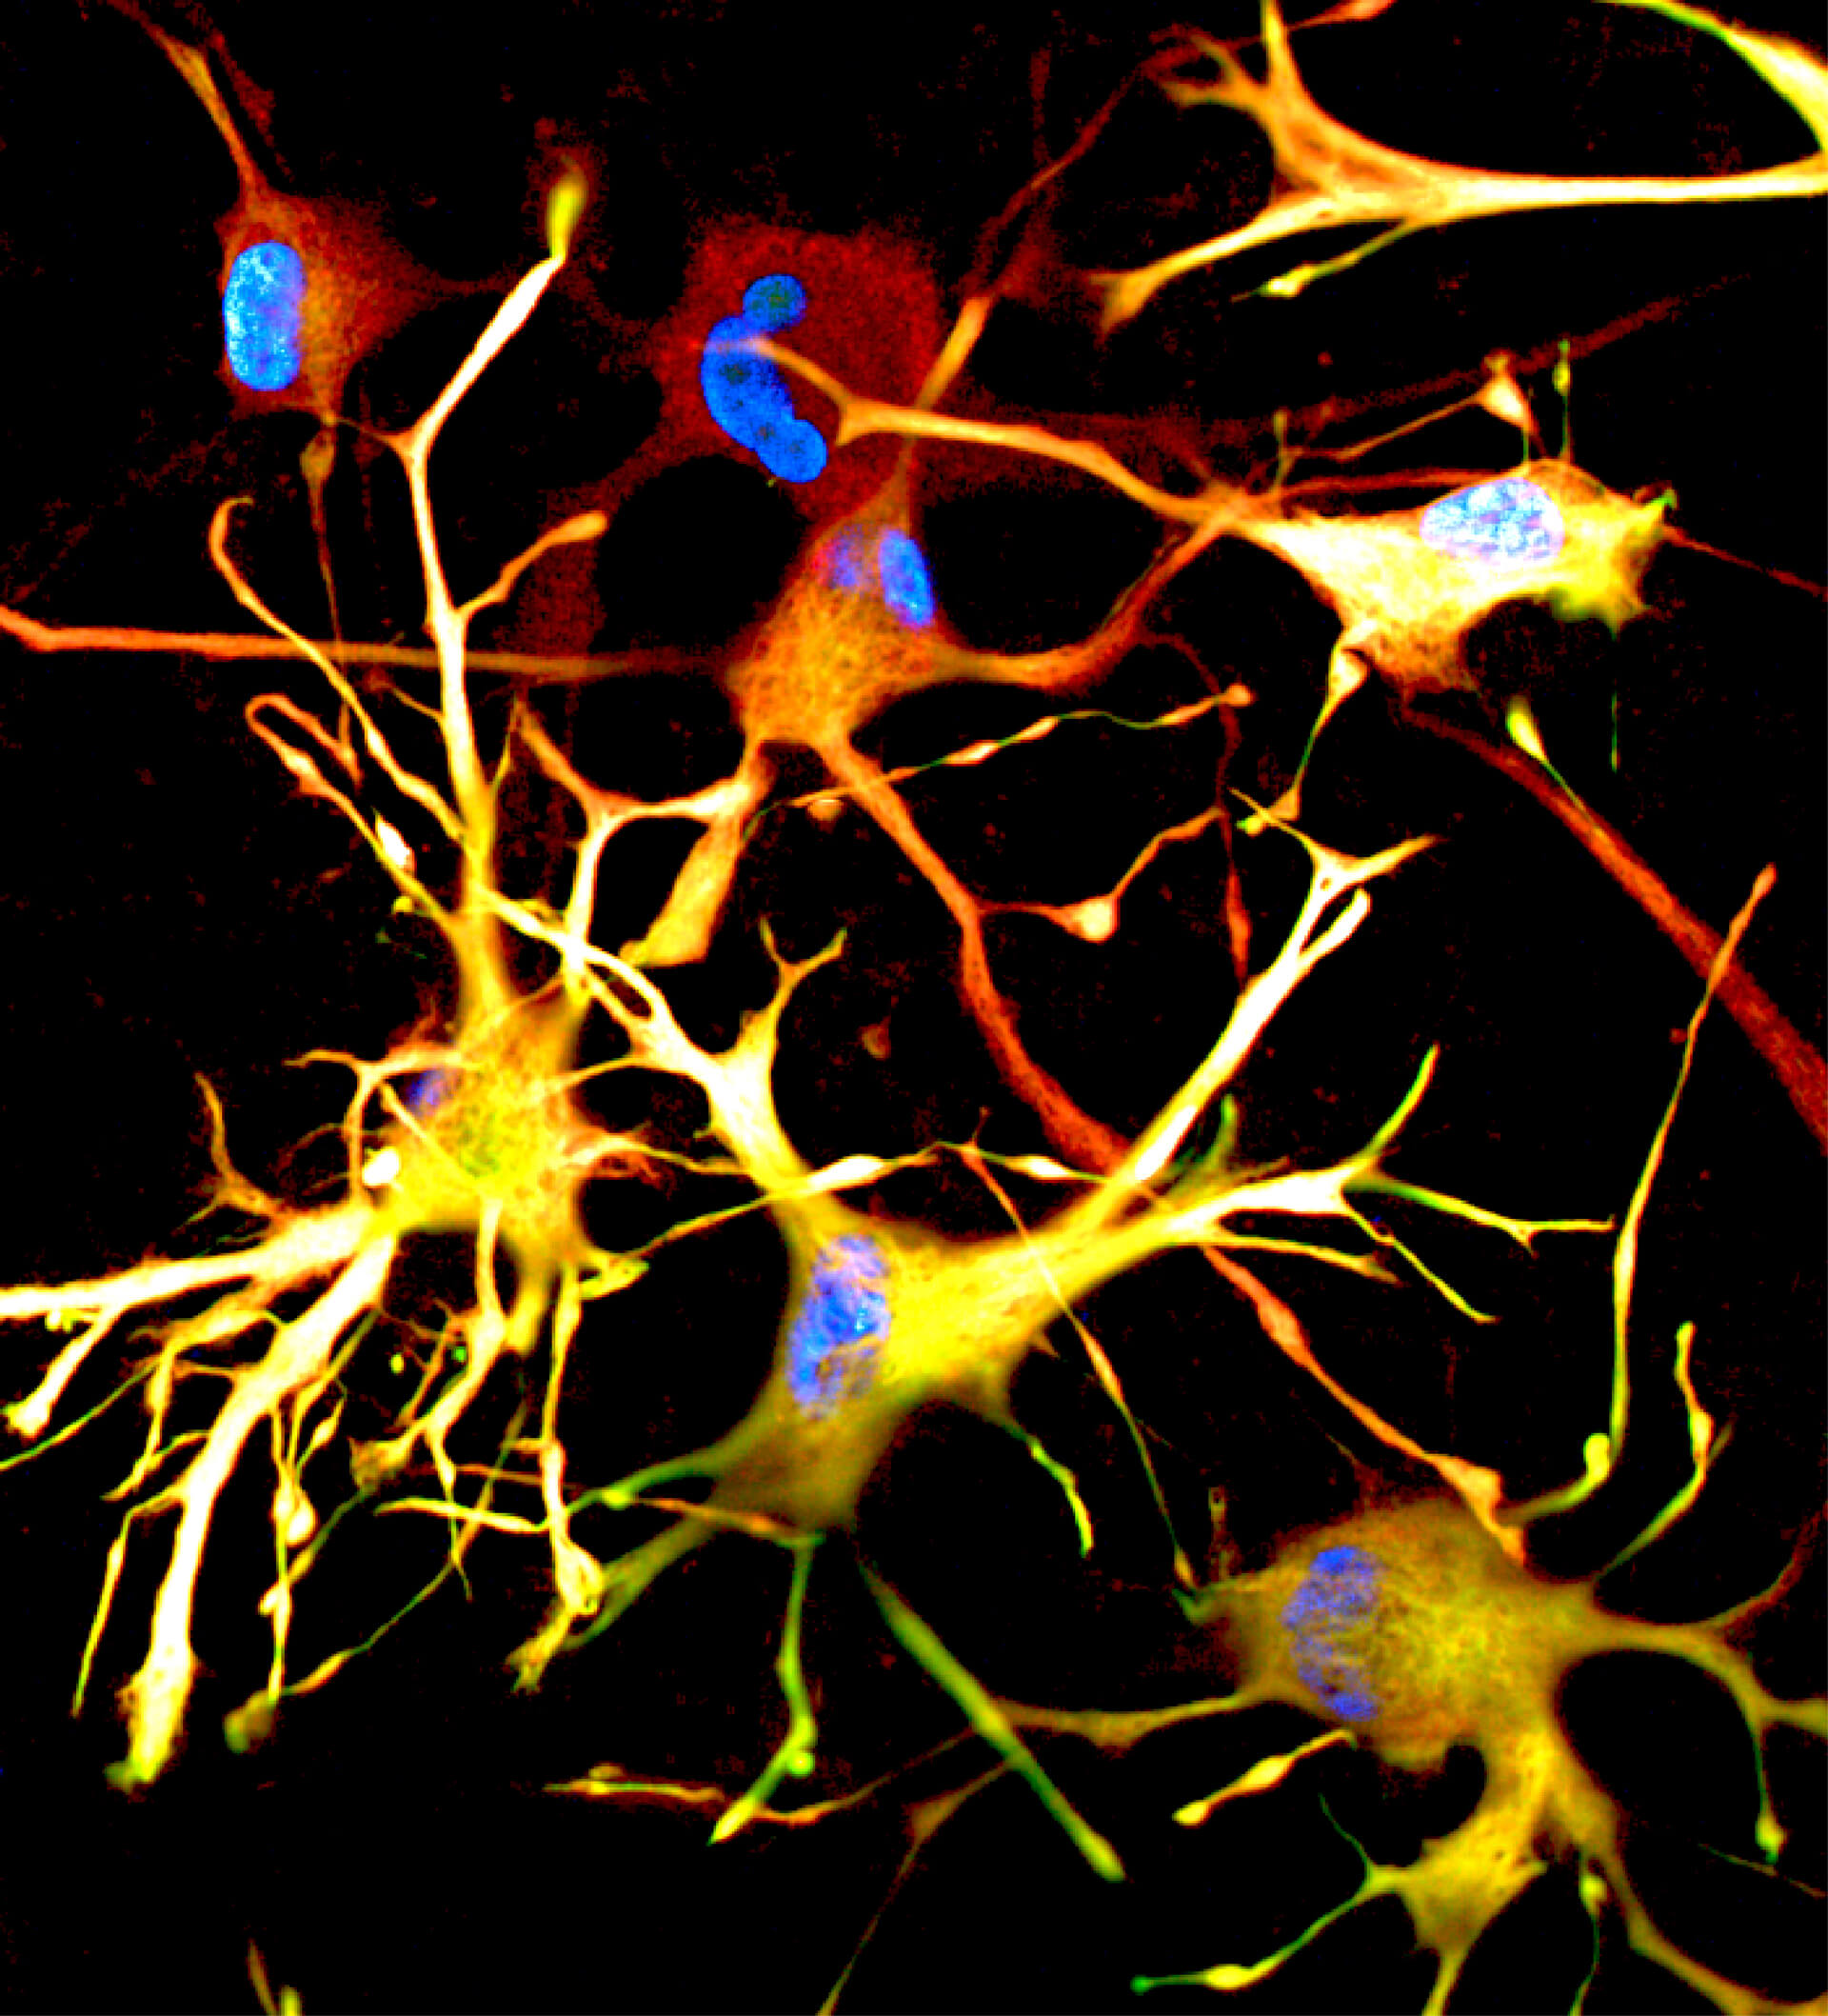

This image is part of the IHB InSight series, featuring compelling scientific images of the latest innovative human model systems work done by IHB scientists. For more images, go to our News feed.

´This image shows mature astrocytes of the central nervous system that were derived from human induced pluripotent stem cells (hiPSC). Astrocytes play crucial roles in maintaining neuronal health, regulating lipid metabolism, modulating synaptic activity, and contributing to the blood-brain barrier. These astrocytes here carry the ApoE4/E4 genotype, a genetic variant strongly associated with increased risk for late-onset Alzheimer’s disease. The ApoE4 variant is known to affect astrocyte function, making these cells invaluable for studying the pathophysiology of neurodegenerative diseases. The cells are stained to highlight the astrocyte markers GFAP (green) and Aqp4 (red), revealing a star-shaped, complex morphology. The generation of these hiPSC-derived ApoE4 astrocytes involved CRISPR Cas9 engineering, along with advanced differentiation and maturation protocols. By achieving a more mature state in culture, these astrocytes provide a human-relevant model to explore disease mechanisms and screen potential therapeutic compounds. This model overcomes previous limitations in astrocyte culture systems, enabling more accurate and impactful research in the field of neurodegenerative diseases. The image was created using immunofluorescence staining and high-resolution confocal microscopy. The astrocytes were cultured and imaged by Sybille Seiler of IHB and pRED NRD, with contributions from Tomasz Chelmicki, Daniel Olivieri, Jonas Fleck, Gray Camp and Lynette Foo.